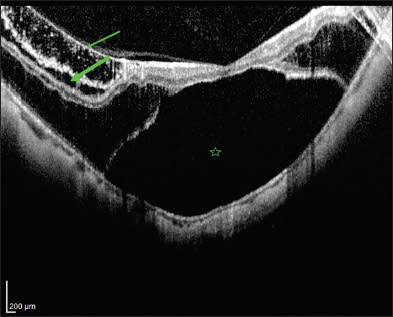

Myopic foveoschisis can be isolated or, more often, accompanied by other macular abnormalities, namely foveal detachment (FD), epimacular structure (EMS), lamellar or full-thickness macular hole (MH), retinal microfolds, and photoreceptor defects at the inner and outer segment (IS/OS) junction7,12-14 (Figure 2).

Figure 2. SD-OCT image of a 60-year-old woman with high myopia and posterior staphyloma demonstrating typical MF (large arrow), premacular structure (small arrow), and foveal detachment (star).

Foveal detachment, characterized by separation between the retinal pigment epithelium and photoreceptor layers, is the most common accompanying finding.10,14 It usually occurs following the formation of the foveoschisis10 and may precede macular hole formation.15 EMS is the hyper-reflective line that appears on some OCT images overlying the inner schisis. This tractional structure could be a partially detached posterior hyaloid, epiretinal membrane, or detached internal limiting membrane.9,10,14 Transmission electron microscopy on the excised EMS has revealed that it is made of fibroblast-like cells, collagen matrix and a very thin posterior hyaloid, and no ILM was found.14